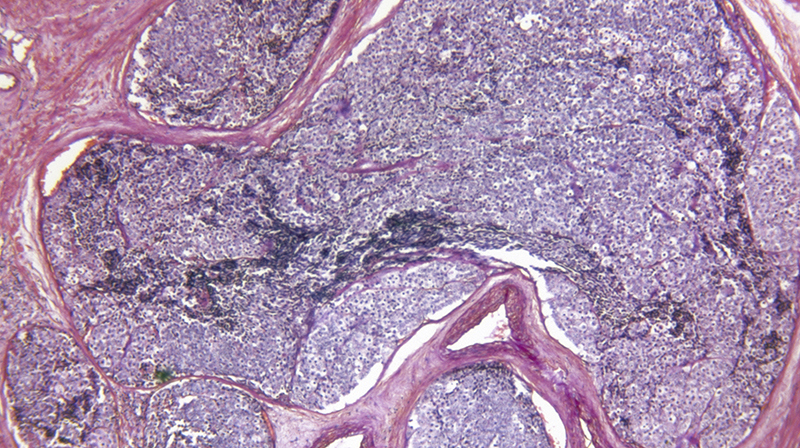

Prostate Cancer Cell Research Adobestock 111509561 PC 3

Series 3 - Spotlight on…understanding cell death

In the next series of webinars we sign the spotlight on a number of methods to trigger cell death from activating death pathways through to immunotherapy.